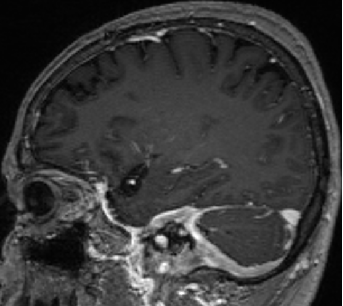

2015-4-1 MRI

2015-4-1

2015-4-3